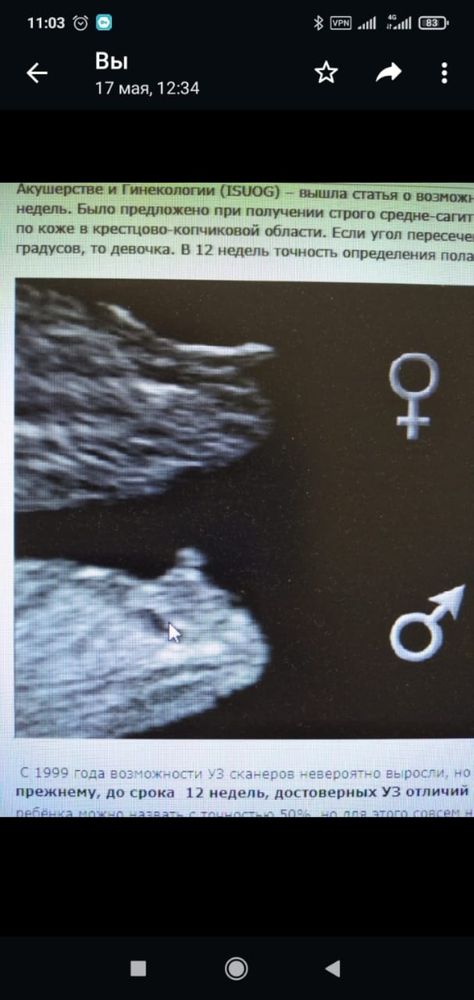

Если эта торщащая «штучка» - это именно бугорок, а не косточка, тогда мальчик. И то, что вы обвели красным - не имеет смысла, смотрят именно по бугорку, тк у девочек и мальчиков на таком сроке они одинаковы.

Евгения , то, что белое - это кость)) В половых органах их же нет😊 А то, что обведено у Вас на фото, надо полагать, половой бугорок. Вроде, мальчиковый. В пример Вы приводите идеальное фото, как в учебнике, но, к сожалению, не каждый узист может такое выдать. Часто ноги в кадр попадают))